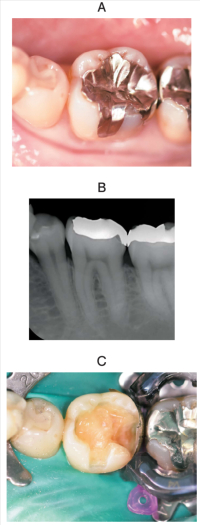

48 歳の女性。下顎左側第一大臼歯の一過性の冷水痛を主訴として来院した。検査の結果、齲触が認められたためコンポジットレジン修復を行うこととした。初診時の口腔内写真、エックス線画像及び処置中の口腔内写真を別に示す。

次に行う操作で正しいのはどれか。2つ選べ。